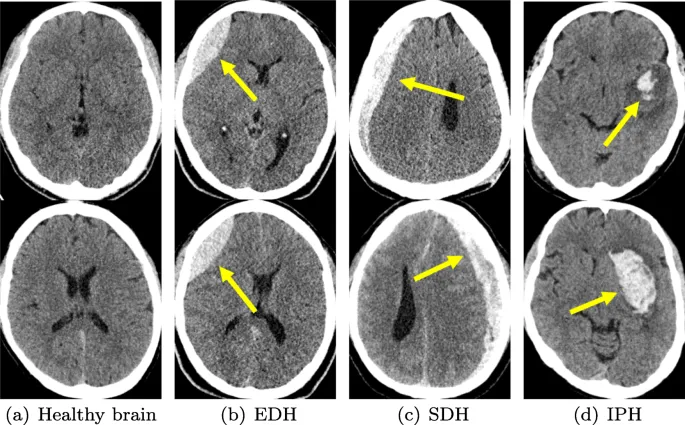

- SDH: Crescent-shaped, crosses sutures. Acute (hyperdense), chronic (hypodense).

- EDH: Lens-shaped (biconvex), doesn't cross sutures. MMA tear. Lucid interval.

Feature Epidural Hematoma (EDH) Subdural Hematoma (SDH) Vessel Middle Meningeal Artery (MMA) Bridging Veins CT Shape Biconvex (lenticular) 📌 Lemon Crescentic 📌 Banana Sutures Does NOT cross CAN cross Clinical Lucid interval Gradual (elderly, alcoholics)

⭐ Epidural hematoma (EDH) is typically arterial and does not cross suture lines, while subdural hematoma (SDH) is usually venous and can cross suture lines.